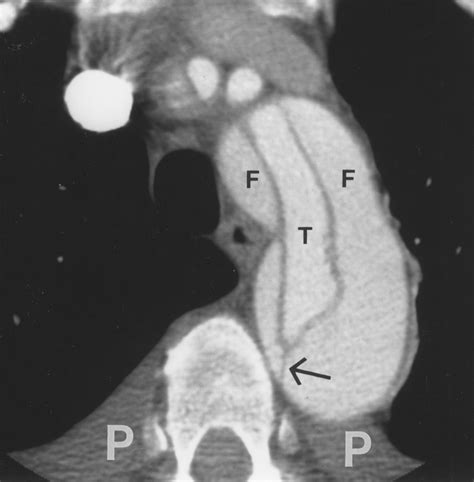

The primary goal of the Aortic Dissection CT is to identify the "intimal flap"—the physical separation of the aortic layers. Radiologists categorize these findings based on the Stanford or DeBakey systems, which help surgeons decide the urgency of the repair. The report will typically detail several critical features:

Intimal Flap The presence of a visible tear separating the true and false lumens.

False Lumen The space formed between the aortic layers that fills with blood.

Clinical management is heavily dictated by the classification determined during the Aortic Dissection CT analysis. The Stanford system is the most commonly used framework in clinical practice:

• Stanford Type A: Involves the ascending aorta. This is a surgical emergency that requires immediate intervention to prevent rupture, cardiac tamponade, or stroke.

• Stanford Type B: Involves only the descending aorta (beyond the left subclavian artery). These are often managed initially with intensive blood pressure control medication in an ICU setting, though some require endovascular repair.